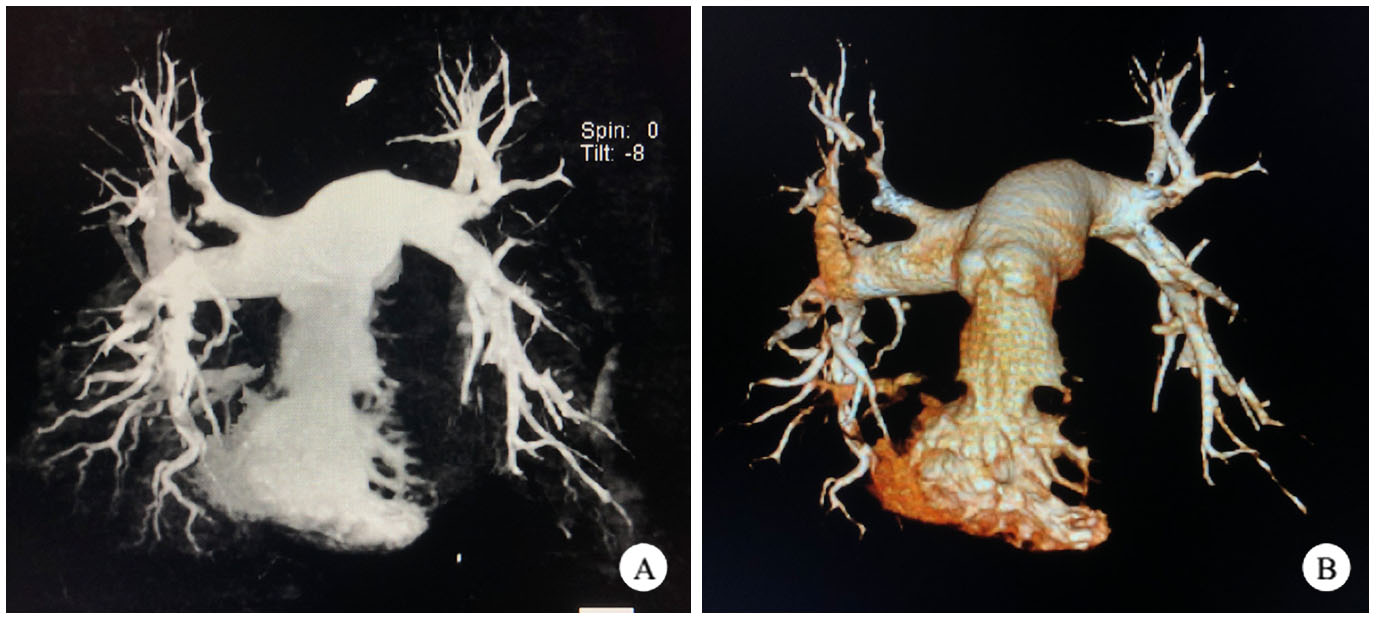

ECMO运行24 h后患者VTI 20.4 cm,EF 55%,右心功能良好,室壁运动协调,导致患者本次心搏骤停的原发病肺栓塞经肺动脉吸栓术后已解除,患者进入撤机流程(视频1见网站附录)。ECMO撤机后患者神经功能完全恢复(视频2见网站附录),呼吸循环稳定。撤机1 d予复查CTPA,提示两侧肺动脉远端血供再通(图 3)。复查双下肢深静脉超声,提示左股静脉及腘静脉内血栓,考虑血栓较大且新近形成,脱落风险大,予介入放置下腔静脉滤网(图 4),并经Angiojet导管吸除股静脉及腘静脉血栓。

| A:冠状位; B:三维重建 图 3 取栓术后CTPA证实肺动脉再通 |